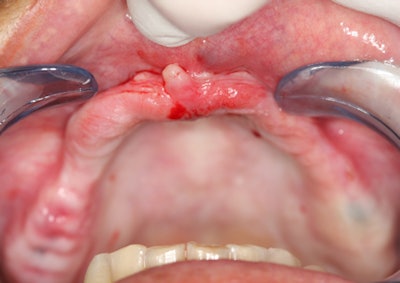

I recently scanned a patient who presented for a consultation to improve his smile and replace a number of missing teeth. The 25-year-old male in good health underwent all the conventional diagnostics, including clinical, periodontal, photographic, and periapical radiographic examination.

A number of findings made it clear that the patient required an enhanced CBCT evaluation to complete a dental examination. As usual, the 3D images were helpful in many ways to present the case, and they gave the patient the necessary information to move forward with a full-mouth rehabilitation.

Please review and consider how the CBCT images aided both diagnosis and case acceptance for these two patients.